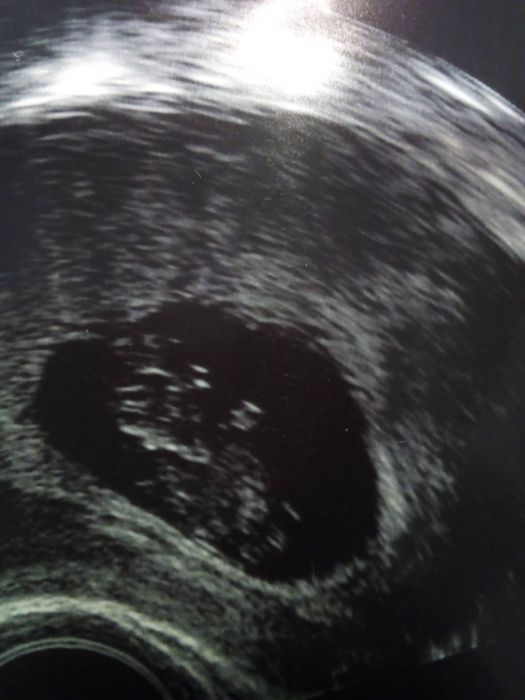

Autor: Daniela 25.11.2018 v 18:53

Ještě fotečka z 21.11. bohužel utz tiskne moc tmavě, tak to není tak krásné jako na obrazovce...